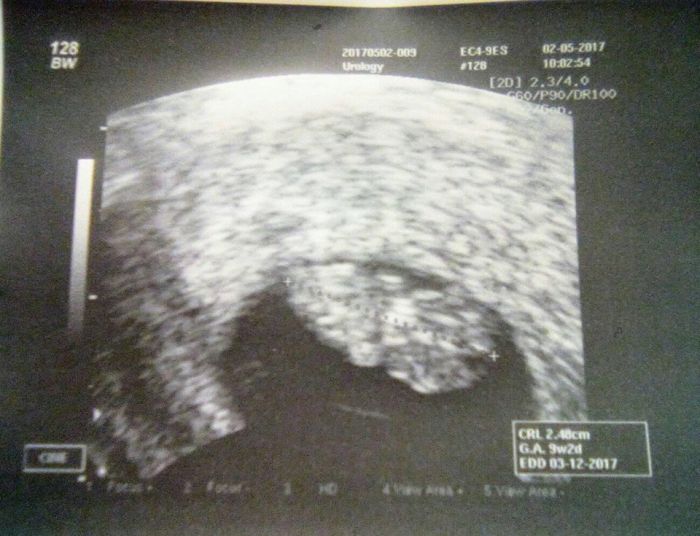

Ahoj holky, já jsem byla dneska poprvé u své gynekoložky, měla radost, že to po těch letech vyšlo

vše ok, mimčo se hýbalo, odpovídá 9+2, dostala jsem dvě fotky, ve čt mám přijít na odběr krve, průkazku mi ještě dát nechtěla, že po ivf je opatrnější a mám přijít znovu za 2 týdny, pak mi jí už vystaví